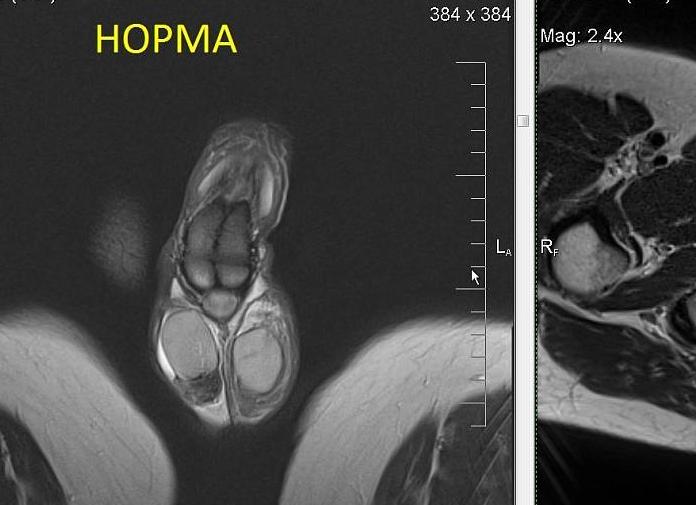

С помощью магнитно-резонансной томографии выявляют нарушения в мягких тканях. Рентген-аппарат определяет травмы и опасные внутренние кровотечения. Первое устройство отличается от второго возможностью представления изображения в трехмерном виде. Чтобы получить изображение в разных плоскостях с помощью рентгена, потребуется многократное рентгеновское облучение. В основе рентгена находятся электромагнитные высокочастотные волны. Они эффективны для диагностики пневмонии, отека и рака легких. Томография работает за счет магнитного поля, с помощью которого специалисты отличают нормальную ткань от патологической. Разница между рассматриваемыми устройствами заключается в том, что МРТ не применяет ионизирующее излучение. Подробнее ...